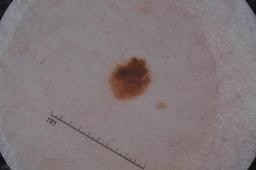

Evaluation set from the ML challenge: SIIM-ISIC Melanoma Classification.